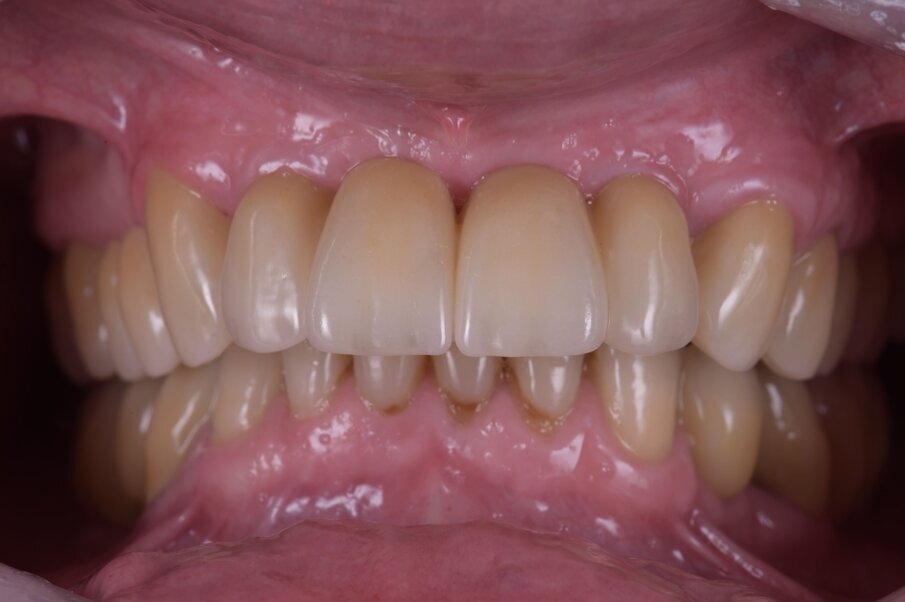

Nell’arcata inferiore dopo il trattamento parodontale abbiamo mantenuto inalterato il V° sestante provvedendo alla rimozione del 3.7 mesio-inclinato con sondaggio e mobilità difficilmente recuperabili e sostituendolo con un impianto. La scelta implantare poco convenzionale ha previsto per la sostituzione bilaterale dei diatorici con impianti in titanio di differente forma e connessione, inserendo bone level (BL) sui premolari e tissue level (TL) sui molari con una protesizzazione mista. La scelta del BL o del TL era rivolta a un aspetto estetico sui premolari e di maggior rispetto tessutale sui molari. Durante le fasi di prova (Fig. 41) si valutano le compressioni dei tragitti transmucosi (Fig. 42), gli eventuali precontatti, si finalizzano le forme e si rileva nuovamente il colore secondo la tecnica di depolarizzazione (Fig. 43). L’appuntamento successivo sancisce l’ottimizzazione dei restauri (Figg. 44, 45). Dopo il posizionamento definitivo dei restauri protesici e l’ottimizzazione dei contatti (Fig. 46) viene nuovamente registrato l’equilibrio di masticazione tramite l’uso del sincronogiografo che registra le forze muscolari confrontando i valori registrati dal momento iniziale pre-trattamento a quello con i provvisori e infine alla stabilizzazione finale, così che nel tempo si possa aver traccia dell’adattamento realizzato (Fig. 47). Il recupero funzionale ed estetico (Figg. 48, 49) rappresentano il traguardo dopo un lungo percorso. Il condizionamento della paziente ha rappresentato un ostacolo nelle libere scelte cliniche segnando di conseguenza l’intero percorso. L’aspetto psicologico ha giocato un ruolo importante nella realizzazione del piano di trattamento, la malattia precedente e il lungo periodo di provvisorizzazione ha arrecato nella paziente un forte disagio. Talvolta quest’aspetto induce il clinico a fare dei compromessi procedurali e anche noi abbiamo cercato di ottimizzare una riabilitazione estetico funzionale correndo dei rischi procedurali a fronte di una richiesta conservativa e talvolta riduttiva nelle procedure chirurgiche. A oggi il follow-up e i controlli di igiene e di verifica della funzione è cadenzato e rigorosamente rispettato dalla paziente. A 5 anni non sono stati evidenziati problemi dei materiali impiegati né tantomeno funzionali (Figg. 50, 51).

Fig. 48_Eseguendo fotografie laterali dx e sx riusciamo a vedere la naturale posizione del labbro superiore a riposo e nel sorriso, confrontandole (Fig. 3) riscontriamo il successo nella rimozione della flangia in resina con una rigenerazione ossea e con la forma coronale, rimuovendo il codice a barra presente in Figura 4.

Fig. 49_A maggior ingrandimento notiamo la naturalezza delle labbra giustamente umettate segno di una fisiologia ritrovata.